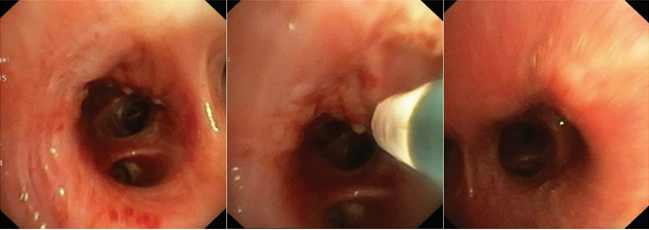

这种情况下,我们首先在硬质支气管镜下用纱布快速填塞右中间段的支气管。填塞后使用可弯曲支气管镜冷冻探头清理右上叶后段和前段的血凝块。当尝试清理右中间段支气管血凝块时,发现气道内还有少量渗血,因此再次使用明胶海绵进行填充,观察没有活动性出血后插入双腔气管支气管插管,支气管镜下确定位置无误,然后转运到导管室进行支气管动脉造影。

图片

图4  冷冻清理支气管中的血凝块